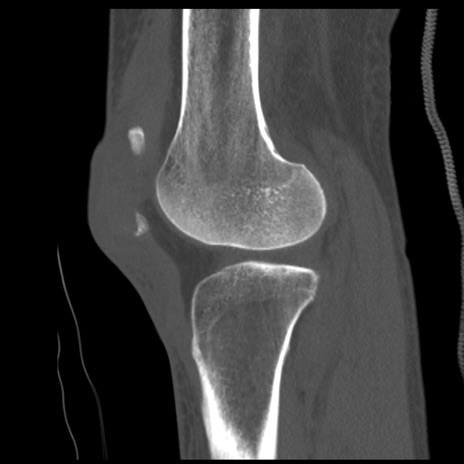

症例28 右膝関節CT(矢状断像)

右膝関節CT

冠状断像